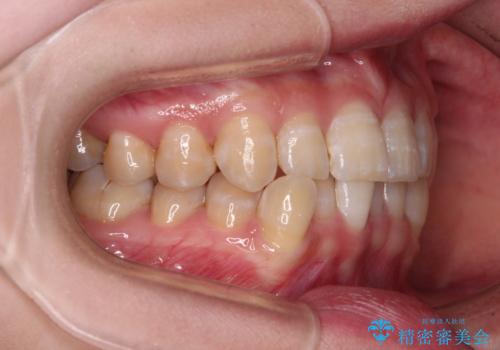

- 下顎の八重歯を気にして来院された患者様です。

マウスピース矯正でもワイヤー矯正でも対応可能であり、マウスピースによる治療を希望されたため、インビザラインを用いることとしました。

下顎前歯にデコボコが集中していたため、顎間ゴムによる後方移動とIPR(歯と歯の間を削ること)により歯列を整えることとしました。

下顎前歯のデコボコが集中しており、奥歯の咬み合わせは、上顎に対して下顎が前方位にある状態でした。下顎の歯列を後方へ移動させる治療はインビザラインの得意とするところですので、1年程度で無事に治療を終えることができました。